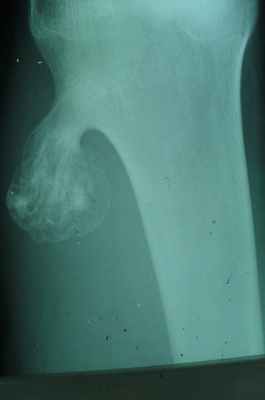

Гигантоклеточная опухоль

(остеобластокластома)

- состоит из клеток 2 типов- многоядерных гигантских и мелких одноядерных,

- поражаются люди в возрасте от 20 до 40 лет,

- локализация бедренная кость - дистальный конец, проксимальный конец б/берцовой кости, дистальный конец лучевой кости. Из плоских костей – тазовые кости и лопатка, очень редкая локализация в позвонках,

- одиночность и изолированность поражения,

- характерно расположение опухоли в эпиметафизраном отделе, который значительно вздут и деформирован, имеет вид крупнобугристого полушария, булавы,

- опухоль доходит до суставного хряща и обрывается,

- растет во всех направлениях, но главный рост происходит вдоль длинной оси кости в сторону с/3 диафиза кости,

- поперечник опухоли может увеличивать нормальный диаметр опухоли в 3-5 раз.

- ячеистый тип - опухоль состоит из отдельных камер, отделенных друг от друга полными и неполными перегородками (мыльные пузыри или неправильные соты),

- корковое вещество раздвигается, вздувается изнутри, истончается, надкостничных наслоений нет,

- при больших опухолях корковое вещество рассасывается и опухоль окружена со всех сторон тонкой скорлупой состоящая из стенок поверхностно расположенных ячеек.

- остеолитический тип – полное отсутствие ячеистого или трабекулярного рисунка, дефект кости вполне гомогенен,

- краевой блюдцеобразный дефект,

- корковый слой на пораженном месте рассасывается, а на границе с дефектом корка заострена, не подрыта и не имеет никаких периостальных наслоений,

- контуры дефекта резкие,

- патологические переломы в 12% случаев.